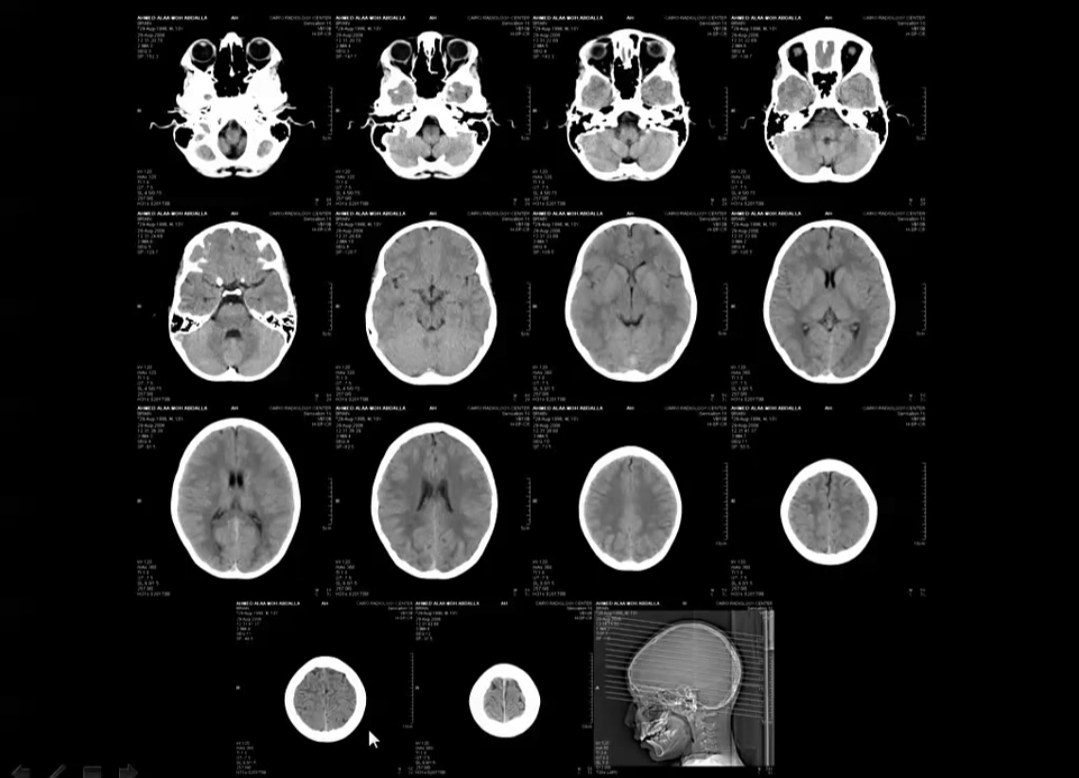

Basics of brain CT scan part III YouTube What Does A Normal Brain Scan Look Like Information to help patients understand their brain mri radiology report. There’s the wrinkled outer layer. On a normal brain mri, you’ll see some key structures that stand out like landmarks on a map. This article lists examples of normal imaging of the brain and surrounding structures, divided by modality and protocol. Healthcare providers use brain mris to. This typically refers. What Does A Normal Brain Scan Look Like.

case study Normal CT brain How to report What Does A Normal Brain Scan Look Like A brain (head) mri scan is a painless test that produces very clear images of the structures inside of your head — mainly, your brain. This typically refers to what is visible on an mri brain scan as “white patches” in the white matter structures of the brain, as seen on specific imaging sequences, representing areas. Information to help patients. What Does A Normal Brain Scan Look Like.

Brain Anatomy on CT Axial Landmarks Normal brain CT. Thi… Flickr What Does A Normal Brain Scan Look Like Lean about the various sections of report including type of exam,. Learn about basic brain anatomy and function, what a normal brain mri looks like, and some abnormal findings that can be discovered on an mri machine. This typically refers to what is visible on an mri brain scan as “white patches” in the white matter structures of the brain,. What Does A Normal Brain Scan Look Like.

Normal Head CT Scan Anatomy Made Simple Neuroradiology YouTube What Does A Normal Brain Scan Look Like Information to help patients understand their brain mri radiology report. Lean about the various sections of report including type of exam,. Healthcare providers use brain mris to. On a normal brain mri, you’ll see some key structures that stand out like landmarks on a map. This article lists examples of normal imaging of the brain and surrounding structures, divided by. What Does A Normal Brain Scan Look Like.

Normal CT BRAIN What Does A Normal Brain Scan Look Like There’s the wrinkled outer layer. This article lists examples of normal imaging of the brain and surrounding structures, divided by modality and protocol. This typically refers to what is visible on an mri brain scan as “white patches” in the white matter structures of the brain, as seen on specific imaging sequences, representing areas. On a normal brain mri, you’ll. What Does A Normal Brain Scan Look Like.